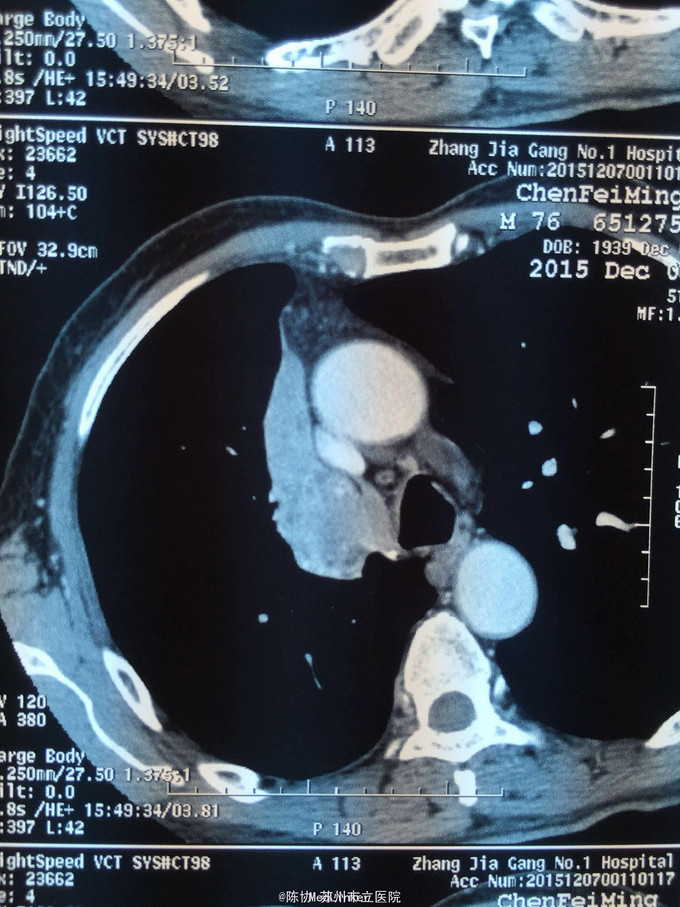

主诉:体检发现右上肺不张半月 77岁男,半月前体检发现右上肺不张,无不适。无消瘦,无咳血,无干咳。去年4月右上肺炎,抗生素治愈,当时CT未见肺肿块。入院支气管镜发现右上支气管开口组织增厚闭塞,开口近侧有隆起约3x3平方毫米,取活检5块病理示中度非典型增生。CT提示在右侧主支气管外侧有30x30平方毫米块影,压迫右上支气管开口处。三大常规和生化检查正常,肿瘤指标正常,TAP正常。

右侧中央型肺癌 重做支气管镜,精于定位找到病症组织,获得病理诊断来指导治疗。 胸外科医生不建议手术,理由是肿瘤位置靠近主支气管和气管,袖状切除不一定看干净。 请问正确的诊断,和比较合理的治疗方法是什么?求助大家思考评论